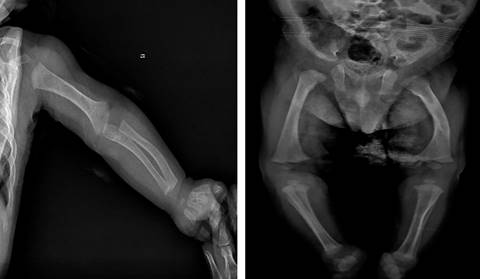

En el control ambulatorio a las 24 semanas de vida, el paciente presentaba adecuada ganancia ponderal, parámetros bioquímicos en límites normales (Tabla 1), y en las radiografías de huesos largos mostraban discreto ensanchamiento metafisario y curvatura anómalas por fracturas previas (Figura 2).